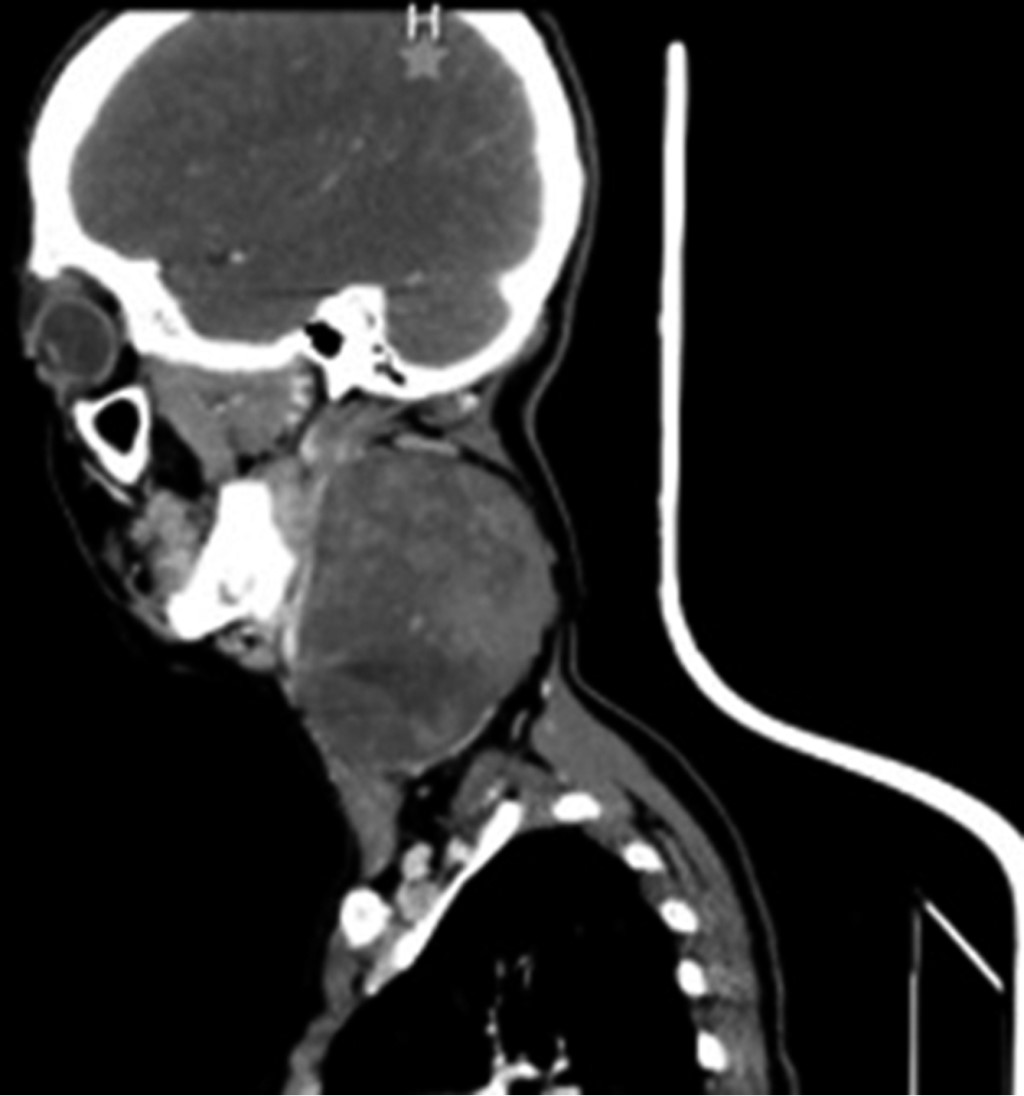

Sin datos de síndrome de respuesta inflamatoria sistémica, inestabilidad hemodinámica o compromiso cardiopulmonar, como complemento diagnóstico se solicita tomografía computarizada, la cual reporta gran masa redondeada de aspecto sólido de bordes regulares, bien delimitados, heterogénea de predominio hipodensa, con pequeñas zonas de menor densidad en su interior, sin identificar calcificaciones, con una densidad entre 24 y 37 UH y que posterior a la administración de medio de contraste intravenoso presenta una densidad entre 33 y 87 UH, localizado en nivel parafaríngeo izquierdo de 6.6 × 7.5 × 9.2 cm, lesión de espacio parafaríngeo izquierdo con sospecha de quiste branquial versus adenoma pleomorfo versus quiste branquial hemorrágico (Figuras 2, 3 y 4).

Figura 2